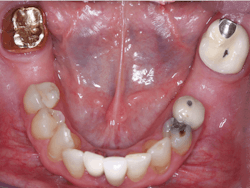

Although this category of restorations is decreasing in use due to implant placement, FPDs are occasionally needed. Clinicians Report Foundation has proven the viability of the original BruxZir in these situations (figure 4).